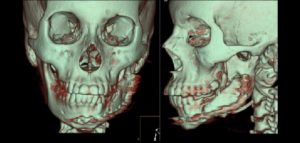

El número de pacientes que requieren prótesis sobre implantes ha aumentado considerablemente en los últimos años. La osteointegración de los implantes dentales es el requisito